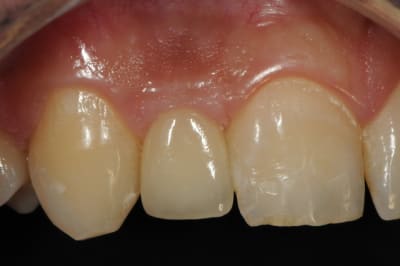

photos finish!!!

à noter...avec le flash...difficile de rendre le "naturel" de ces restaurations(teintes très claires)...après petite gingivoplastie pour harmoniser la hauteur des collets...(surtout pour 12...)